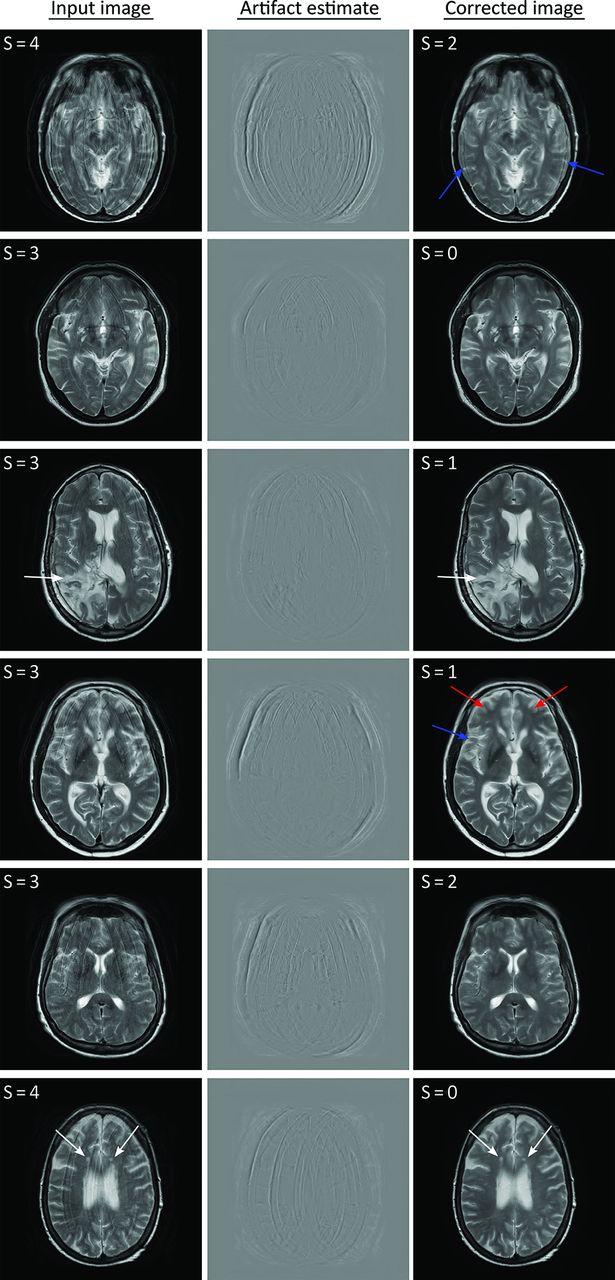

Similar results were obtained for the test dataset with real motion cases, as shown exemplarily in Fig 5. Substantial improvement of image quality was observed for nearly all cases, often with no, or only minor, residual artifacts (marked by blue arrows). Similar to the synthetic test data, minor blurring was observed in some parts of the images (marked by red arrows), typically in regions with severe artifacts in the input images. Most interesting, the algorithm showed robust performance even for radiologically detectable brain pathologies that were not present in the training dataset, such as the lesions in the third and sixth rows of Fig 5 (marked by white arrows), suggesting that the FCN appropriately targeted the motion artifacts only and left the underlying image data relatively unaltered.

Examples of the performance of the network on real-world test data. Residual artifacts and regions of residual blurring are indicated by blue and red arrows, respectively. White arrows indicate lesions where the network removed the motion artifacts despite the lack of such structures in the training dataset. The numbers in the top left of the images are the scores given by the neuroradiologist.